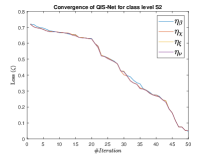

The suitable tailoring of the phase angle in the Hadamard gate advocates the stability of the QFS-Net or its convergence which is very crucial for self-supervised networks where the loss function (here error function) is dependent on the interconnection weights. Hence, the phase angles are evaluated using and as given in Equations 18 and 21, respectively. It is worth noting that the qutrit based quantum neural network provides faster convergence compared to the classical neural networks. This is due to the fact that whereas the classical neural networks are formed using the multiplication of input vector and the weight vector guided by an activation function, the quantum-based networks incorporate the frequency components of the weights and their inputs thereby enabling faster convergence of the network states. This inherent novel feature of the quantum neural networks facilitates the qutrit based fully self-organized quantum algorithm to be employed in QFS-Net to converge super-linearly, as shown in Figure 3. The loss function cum QFS-Net network error function is defined on quantum measurement in the following way.

| (37) |

where, represents the true interconnection weight terms of the inter-connection weights as expressed using the Hadamard gate () at an instance (). is a coherent error function of and . Convergence analysis of the proposed qutrit-inspired QFS-Net is provided in Appendix Section -A and demonstrated experimentally with qubit embedded QIS-Net [39] as shown in Figure 3. It can be summarized that the convergence of the QFS-Net is faster than that of the QIS-Net and also follows super-linearity. This claim is also substantiated by the number of iterations required to converge for each image slice in QFS-Net and QIS-Net as illustrated in Figure 4.